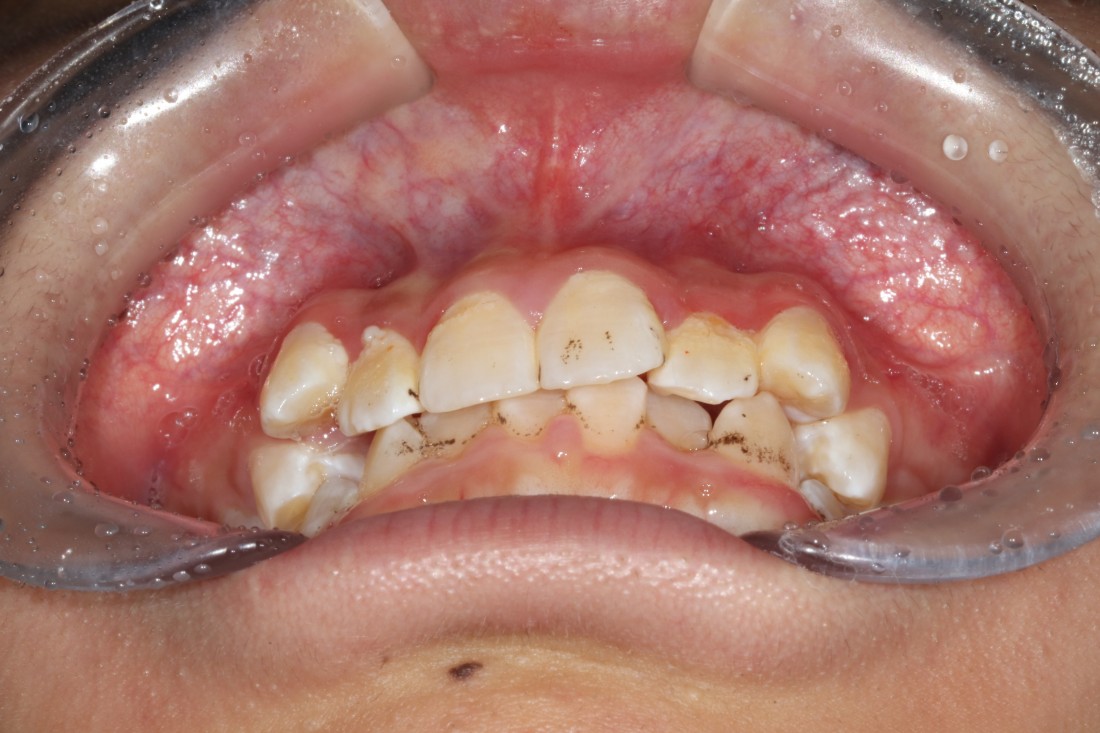

10대 청소년 학생들을 만나다보면

다른 사람들과 마주치거나 대화하는 것도

불편해하는 경우들이 보이는데요.

교정진료 역시 조용한 공간에서

프라이빗하게 받고 싶어하는

경우들이 더 많은 것 같습니다.